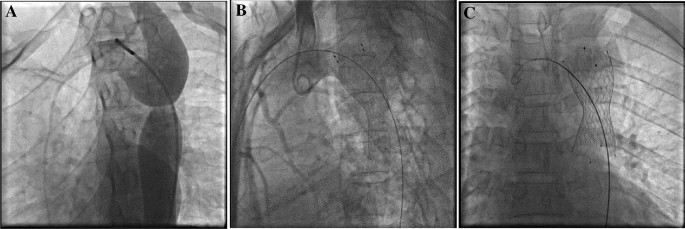

Our results showed successful operation was achieved in all patients (125, 100%) following self-expandable stenting implantation, and 127 stents were used (Fig. 1). The stent diameter was between 18 and 32 mm, and the stent length was 60 mm, which was fixed for all patients.

Intraoperative angiographic monitoring; (A) before and (B,C) after stent implantation.